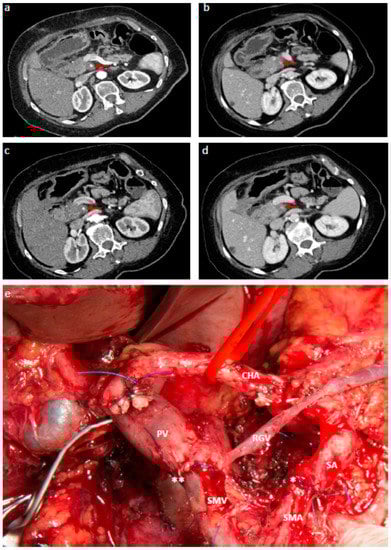

- Hackert, T.; Strobel, O.; Michalski, C.W.; Mihaljevic, A.L.; Mehrabi, A.; Muller-Stich, B.; Berchtold, C.; Ulrich, A.; Buchler, M.W. The triangle operation-radical surgery after neoadjuvant treatment for advanced pancreatic cancer: A single arm observational study. HPB 2017, 19, 1001–1007. [Google Scholar] [CrossRef] [PubMed]

- Inoue, Y.; Saiura, A.; Yoshioka, R.; Ono, Y.; Takahashi, M.; Arita, J.; Takahashi, Y.; Koga, R. Pancreatoduodenectomy with systematic mesopancreas dissection using a supracolic anterior artery-first approach. Ann. Surg. 2015, 262, 1092–1101. [Google Scholar] [CrossRef] [PubMed]

- Klompmaker, S.; van Hilst, J.; Gerritsen, S.L.; Adham, M.; Teresa Albiol Quer, M.; Bassi, C.; Berrevoet, F.; Boggi, U.; Busch, O.R.; Cesaretti, M.; et al. Outcomes after distal pancreatectomy with celiac axis resection for pancreatic cancer: A pan-european retrospective cohort study. Ann. Surg. Oncol. 2018, 25, 1440–1447. [Google Scholar] [CrossRef] [PubMed]

- Klompmaker, S.; Peters, N.A.; van Hilst, J.; Bassi, C.; Boggi, U.; Busch, O.R.; Niesen, W.; Van Gulik, T.M.; Javed, A.A.; Kleeff, J.; et al. Outcomes and risk score for distal pancreatectomy with celiac axis resection (dp-car): An international multicenter analysis. Ann. Surg. Oncol. 2019, 26, 772–781. [Google Scholar] [CrossRef] [PubMed]

- Yoshitomi, H.; Sakai, N.; Kagawa, S.; Takano, S.; Ueda, A.; Kato, A.; Furukawa, K.; Takayashiki, T.; Kuboki, S.; Miyzaki, M.; et al. Feasibility and safety of distal pancreatectomy with en bloc celiac axis resection (dp-car) combined with neoadjuvant therapy for borderline resectable and unresectable pancreatic body/tail cancer. Langenbecks Arch. Surg. 2019, 404, 451–458. [Google Scholar] [CrossRef] [PubMed]

- Takasaka, I.; Kawai, N.; Sato, M.; Tanihata, H.; Sonomura, T.; Minamiguchi, H.; Nakai, M.; Ikoma, A.; Nakata, K.; Sanda, H. Preoperative microcoil embolization of the common hepatic artery for pancreatic body cancer. World J. Gastroenterol. 2012, 18, 1940–1945. [Google Scholar] [CrossRef] [PubMed]